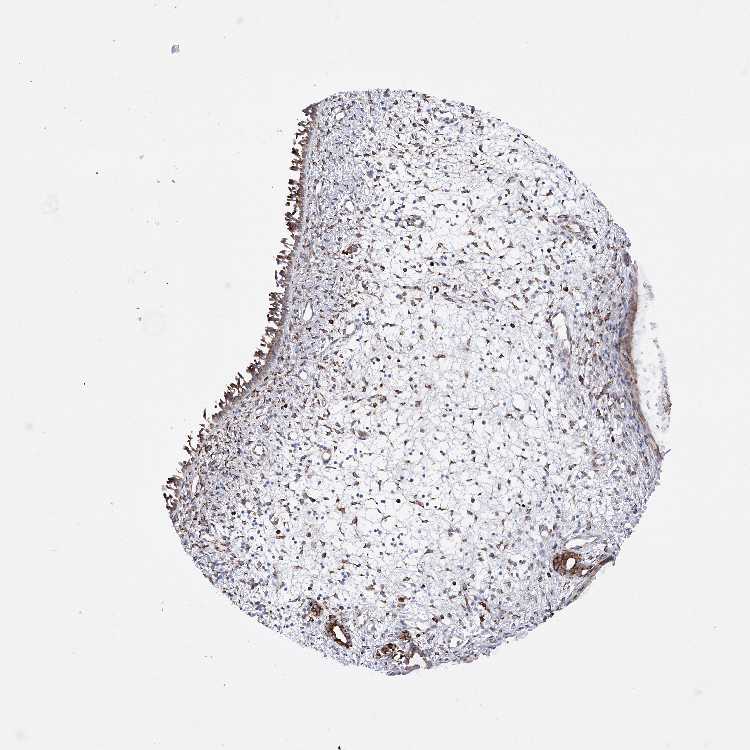

EFCAB2